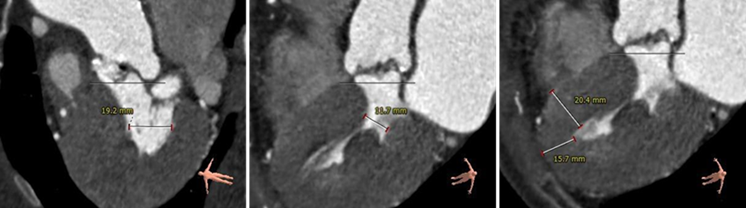

主动脉根部评估

Type1型二叶瓣,右无冠窦发育不全,交界处形成非钙化嵴,伴有瓣叶严重纤维增厚。

右冠高度11.8mm,左冠高度19.3mm,双侧瓣叶长度小于瓣叶附着缘到冠脉开口距离,冠脉遮挡风险较小。

主动脉瓣环与水平面夹角77°,呈横位心。

瓣环上解剖评估

瓣环上轻度钙化,瓣叶纤维增厚明显,瓣上最狭窄处周长:59.5mm,直径:18.8mm。

左心室解剖评估

左心室腔小、心肌肥厚,术中超硬导丝、球囊、瓣膜胶囊腔的压迫下均有可能出现急性大量主动脉瓣反流而导致低血压甚至循环崩溃的风险。